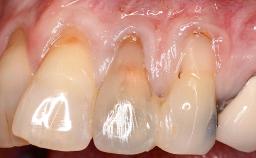

Implant Placement in the Esthetic Zone and Coverage of Multiple Gingival Recessions

This case illustrates use of a modified ‘tunnel’ technique, which has been shown to be highly effective in root coverage procedures. The tunnel technique is used to achieve soft-tissue augmentation across the anterior area, including the planned implant site, using collagen matrix as grafting material. The patient is a 47-year-old woman with high esthetic expectations. Her main concern was the appearance of the anterior teeth and their “elongation”.

Soft Tissue Anatomy Intact Defective